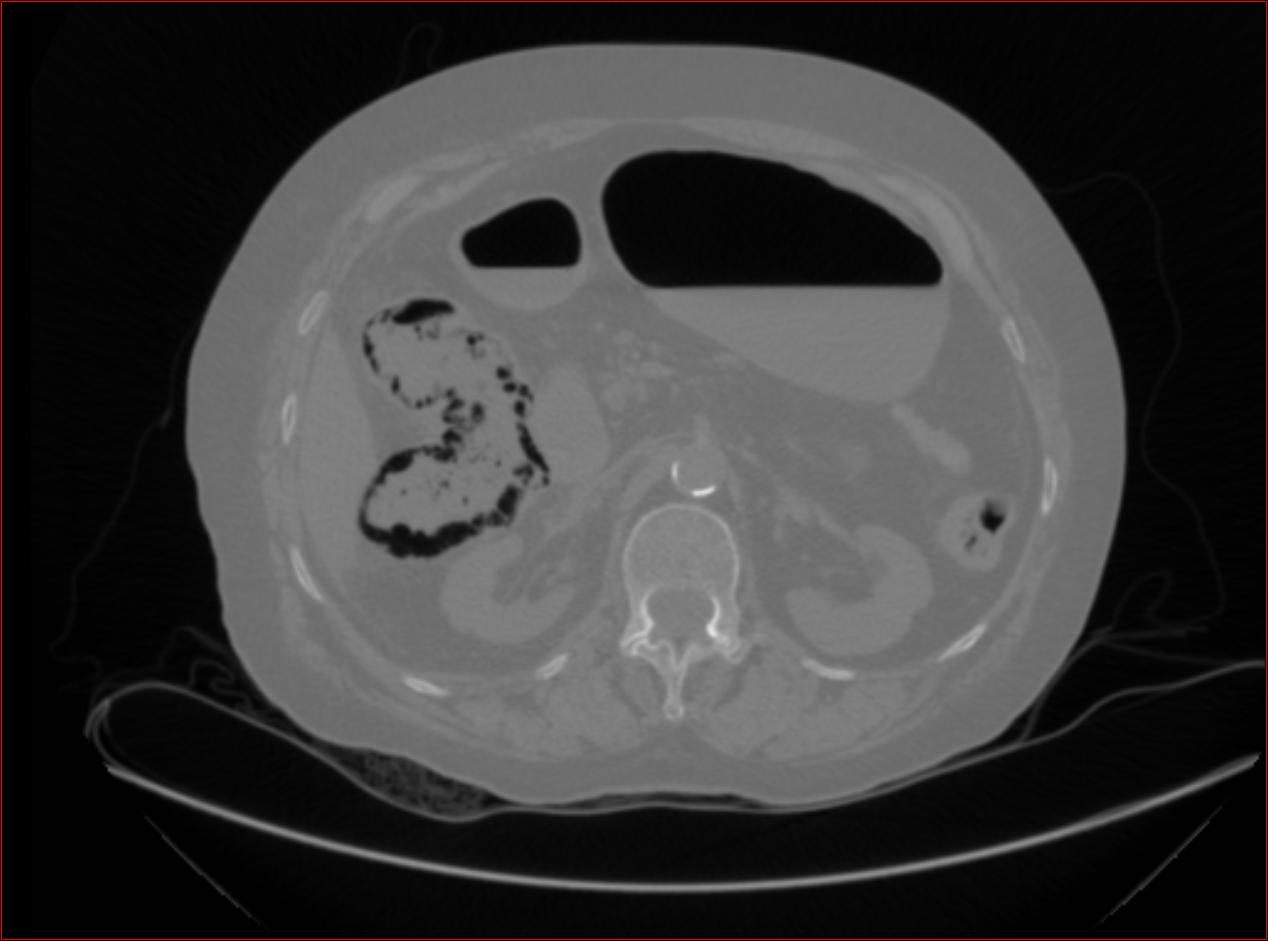

op: gangrenosus (infectios eredet)

- Appendicitis